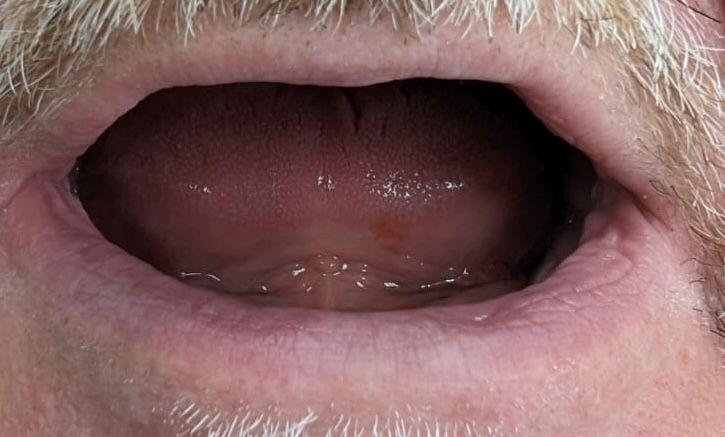

Установка съемного протеза

Установка съемного протеза

Установка съемного протеза

Специалисты стоматологической клиники «Доктор Дент» изготовили высокоэстетичные съёмные протезы, теперь наш пациент может нормально кушать и снова улыбаться!